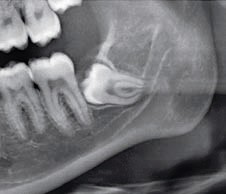

Coronectomie verstandskies